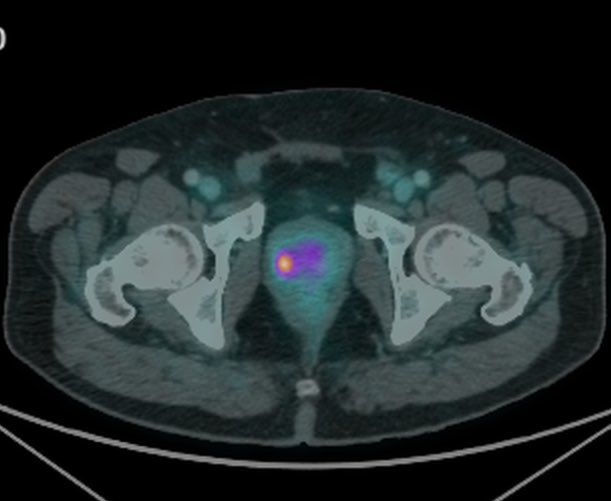

First ThuFLEP procedure successfully performed in Chile with Urolase+ Premium We are proud to share that the first #ThuFLEP procedure in Chile using the Urolase+Premium laser system has been successfully completed at @FelixHfb , with the strong support of our trusted partner IMV MED CHILE. The surgery was performed by Dr. @JIgnacioAcuna and involved a prostate of 50 cc with a non-simple anatomical configuration, further complicated by cystolithiasis with a 17 mm bladder stone. Despite these factors, the entire operation was completed in just 45 minutes. The patient was discharged within 24 hours, underscoring the efficiency and favorable recovery profile of the procedure. @JIgnacioAcuna highlighted the performance of the #DissectPulse mode, noting its precision in anatomical dissection, controlled tissue interaction, and effective hemostasis. According to his feedback, the laser performed excellently and efficiently throughout the case. We sincerely thank IMV MED CHILE for their professional support and collaboration in bringing advanced Thulium Fiber Laser (TFL) technology to Chile. Congratulations to @JIgnacioAcuna and the entire team at @FelixHfb on this achievement. #UrolasePremium #ThuliumFiberLaser #LaserUrology #Endourology #ChileHealthcare #VPGLaserOne